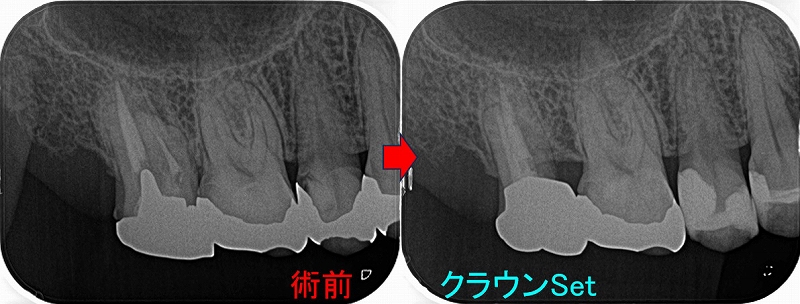

レントゲン

今の所問題無さそうに見えるが経験上、たぶん痛んだ右下6の神経は死んで膿んでくるはず

膿むのを待って根管治療をしてもいいが根管治療の成功率は10%程度下がるので、

早目に根管治療した方がいいと説明

そこから2週間後の来院時

また大きく痛み出したので根管治療を行うことに

2025 EEdental OZU (2).jpg

歯の神経は根の先から少し出血はあったものの、殆ど出血はなく死んだような感じで神経でした。

患者さんにも動画を見てもらい、たぶんこの歯が痛みの原因だと思いますが、大きな虫歯などの直接の原因は分からなかったと説明

*そうなると考えられるのは咬合力

8ヵ月ほど仮歯で生活してもらい痛みや腫れがでないのを確認して

2025 EEdental OZU (3).jpg

ゴールドクラウンを製作